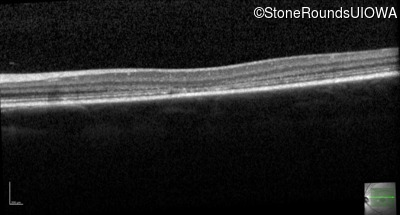

Age at visit: 17 years

Age at visit: 18 years

Age at visit: 20 years